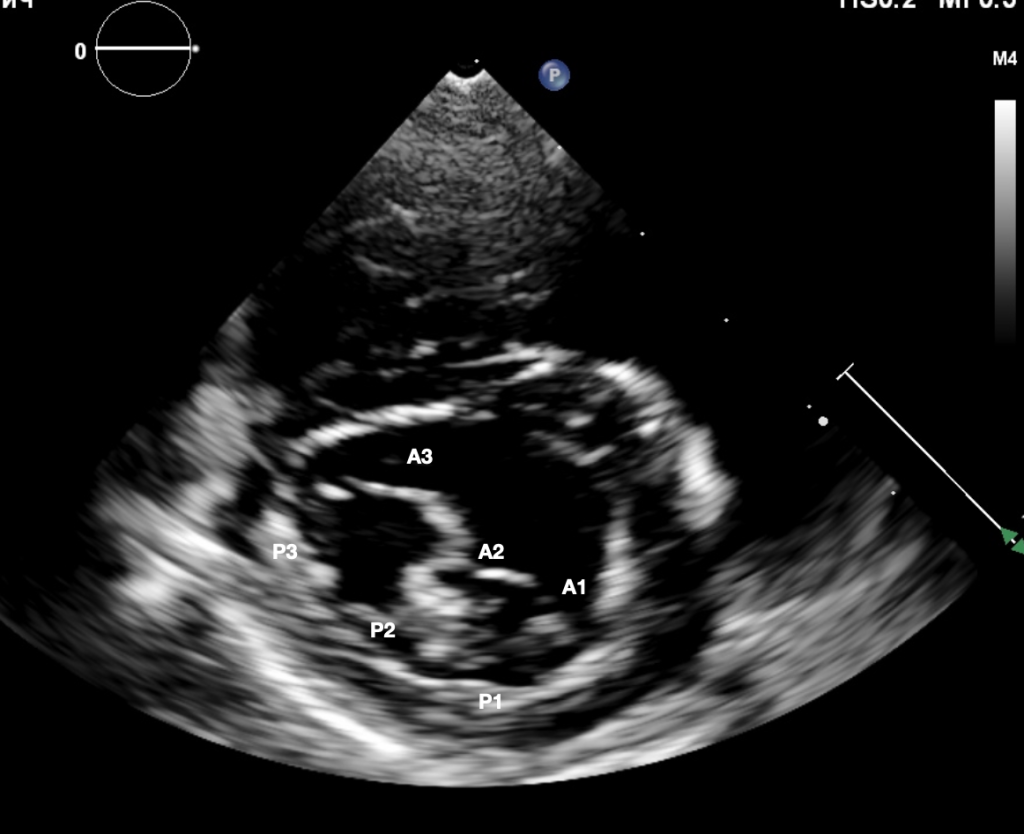

Фото 5-7. Двухмерная эхокардиография, правая парастернальная проекция, короткая ось, срез на уровне створок митрального клапана: значительное улучшение коаптации створок митрального клапана, регургитационные потоки формируются по краям от зоны их стягивания (фото 5); створки клапана стянуты край-в-край в сегменте А2, что обеспечивает основную пропускную способность клапана через зоны А1–Р1 и А3–Р3 (фото 6). Выраженное обратное ремоделирование миокарда левого желудочка (фото 7): уменьшение конечно-диастолического нормализованного размера ЛЖ до 1,3 (до операции КДРн – 1,9).